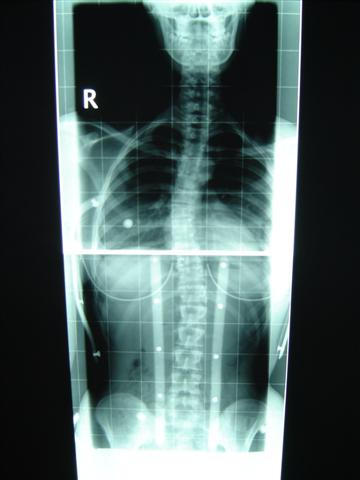

ich war heute in Dresden zum Röntgen gewesen. Musste erst zur Anmeldung, den Schein fürs Röntgen holen und dnan zum Röntgen gehen. Dort stand oben, das ich nur im Tgaeskorsett geröngt werden soll. Wir uns dann beschwert, weil aj nciht im Nachtkorsett geröngt wurde. Also ham se bei der Anmdelung vom dem Orthopädiehaus angerufen und ich konnte doch noch geröngt werden. Und als der Oberarzt die Röbis vermessen hat konnte er es fast selber nicht fassen!! Mein Tgaeskorsett korrigiert die lumbale Krümmung von 37° auf 12° !!!!! Ihr könnt euch gar nicht vorstellen, wie happy ich in dem Moment war, weil ich da die ganze Zeit an Fine und ihre Korsetts denken musste. Meine obere Krümmung wird im Tageskorsett nicht korrigiert, weil diese sehr weit oben sitzt und mein Arm einschläft, wenn er angehoben wird. Aber von den 34° ohne Korsett sind 28° es steht zwar 18° auf dem röbi, aber der Unterschied zu den 12° ist doch zu groß. Wir haben die Röbis auch fotografiert, ich stelle die Bilder dann demnächst hier rein. Im Nachtkorsett ist die untere Krümmung 13 °, und weil die irgendiwe im Liegen nicht die ganze WS röntgen können, kann die obere nicht vermessen werden

Noch mal die Werte im Überblick:

1. Röntgen, 1.3.05: 29° im BWS-Bereich, 32° in der LWS

2. Röntgen, 25.4.05: 34° in der BWS und 37° in der LWS (beides um 5 grad verschlechtert, die Ärzte hatten mir nicht mehr zu viel Hoffnungen gemacht)

3. Röntgen im Korsett, 29.8.05: 28° und 12°